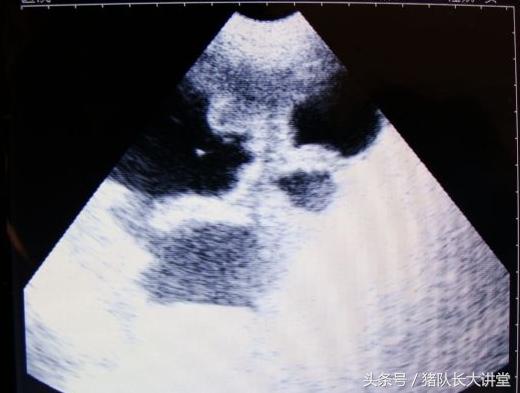

27天图

A、可以较为准确的测出是不是有小猪,具体使用办法,根据说明使用,大家也可以提出问题;关注,一般你检测有的就是有了,单是检测没有的时候应该多观察;